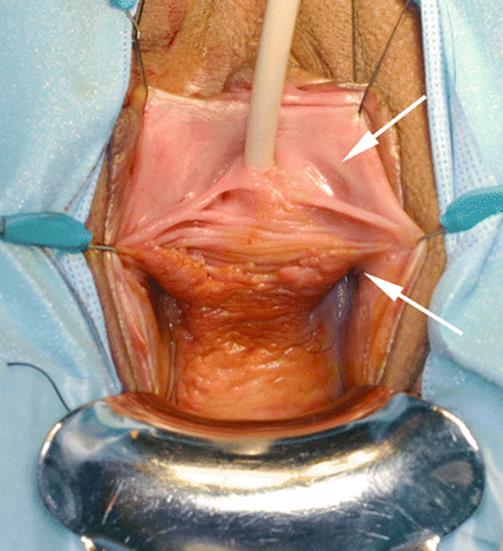

Fig. 8.4

Marsupialization of the cyst was performed. An incision was made in the inner aspect of the vagina medial to the labial minora, the cyst was opened, and the margins of the cyst were anastomosed to the vaginal wall. Arrow shows the line of anastomosis between the cystic wall and the inner aspect of the labia majora